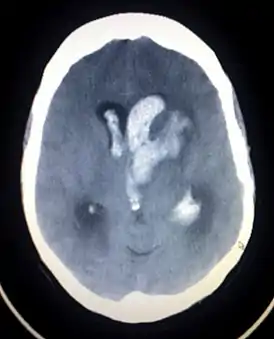

![]() Компьютерная томограмма спонтанного внутримозгового кровоизлияния с прорывом крови в желудочки головного мозга | |

Компьютерная томография — метод выбора в диагностике внутричерепных кровоизлияний.